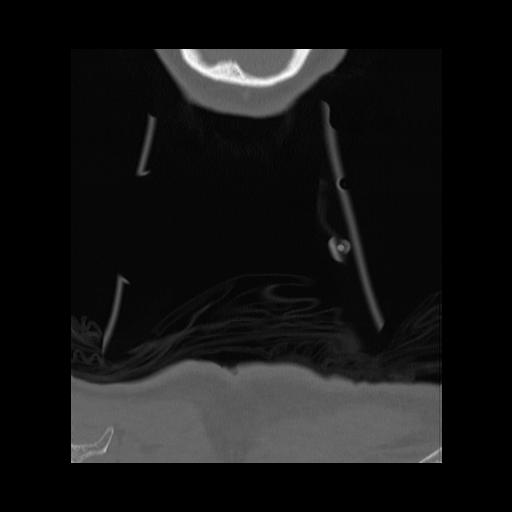

16 HUESO,,Coronal,2.000,HUESO,Coronal,